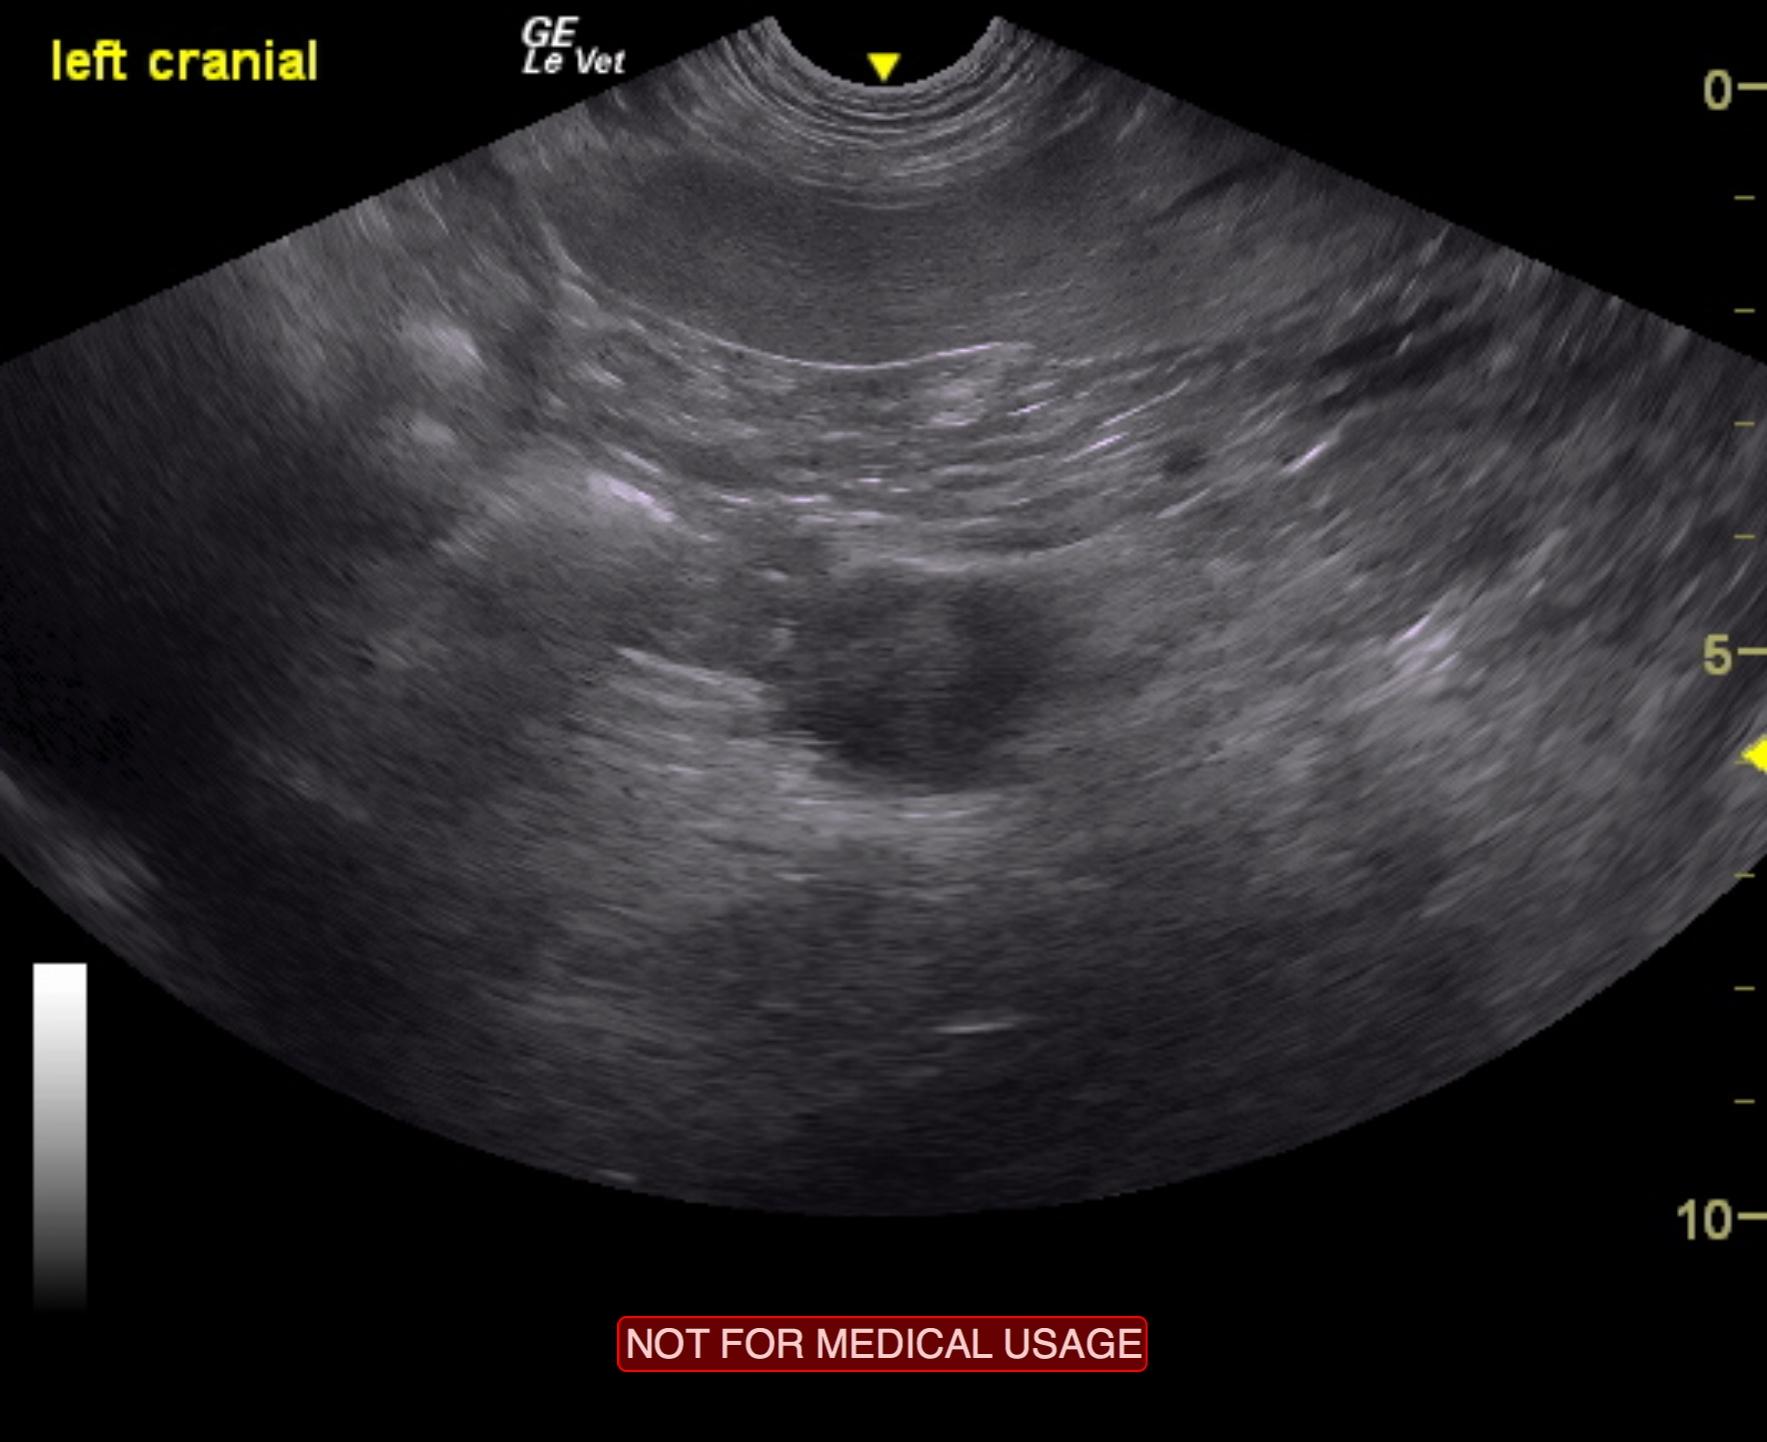

The left pancreatic limb revealed a hypoechoic, 2.0 cm structure, which demonstrated an irregular contour. This may represent a metastatic lymph node or primary mass. The appearance is consistent with insulinoma. Slight, hypoechoic nodular change was noted adjacent to it and measured 1.0 cm.

Given the patient’s history, these images are strongly consistent with insulinoma, with potential local lymph node metastasis. There was no evidence of metastatic lesions in the liver. However, the liver should be inspected at the time of surgery, as micrometastasis is a common event in presumed insulinoma.